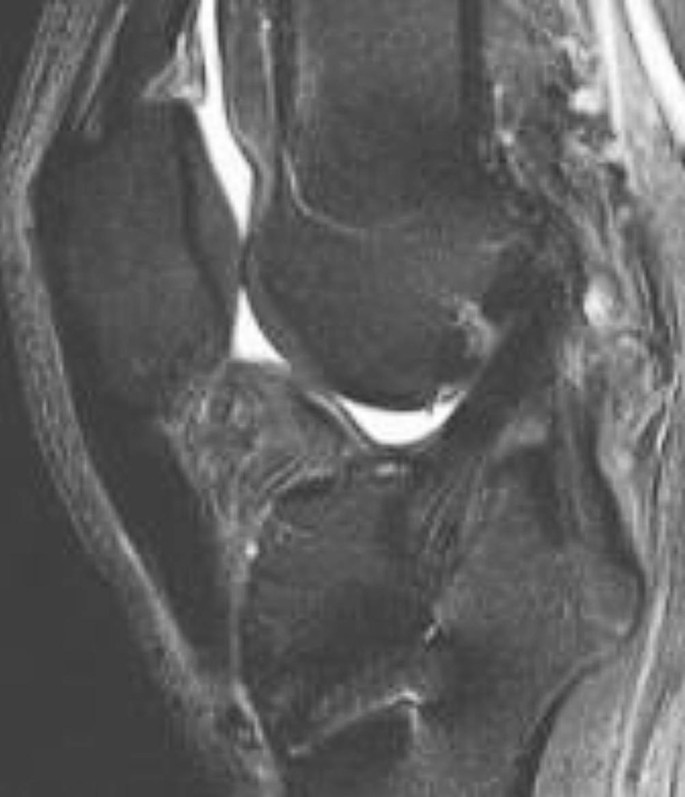

Komplette Ruptur

Eine frühzeitige VKB-Plastik-Ruptur innerhalb der ersten 6 Monate nach Operation kann auf eine inkorrekte Position der Bohrkanäle oder auf ein fehlendes Einwachsen der Plastik zurückzuführen sein. Ein spätes Versagen der Plastik nach mehr als 6 Monaten ist durch ein wiederkehrendes Trauma verursacht.

Die frische Ruptur ist durch ein hohes T2-Signal (Ödem) der Bandstümpfe sowie durch Flüssigkeit zwischen den separierten Stümpfen und im Gelenkraum gekennzeichnet (Abb. 8). Bei einer chronischen Bandruptur findet sich Granulationsgewebe zwischen den Stümpfen, allerdings können sich die Bandstümpfe auch teilweise resorbieren und die restlichen Anteile des Bandes können von umgebenden synovialem Gewebe in der MRT maskiert werden.

Abb. 8

figure 8

Komplette VKB(vorderes Kreuzband)-Plastik-Ruptur: In der fettunterdrückten protonengewichteten Sequenz sind die Stümpfe der Plastik separiert, und Flüssigkeit ist zwischen den Stümpfen erkennbar (Pfeil), was auf ein akutes Trauma hindeutet